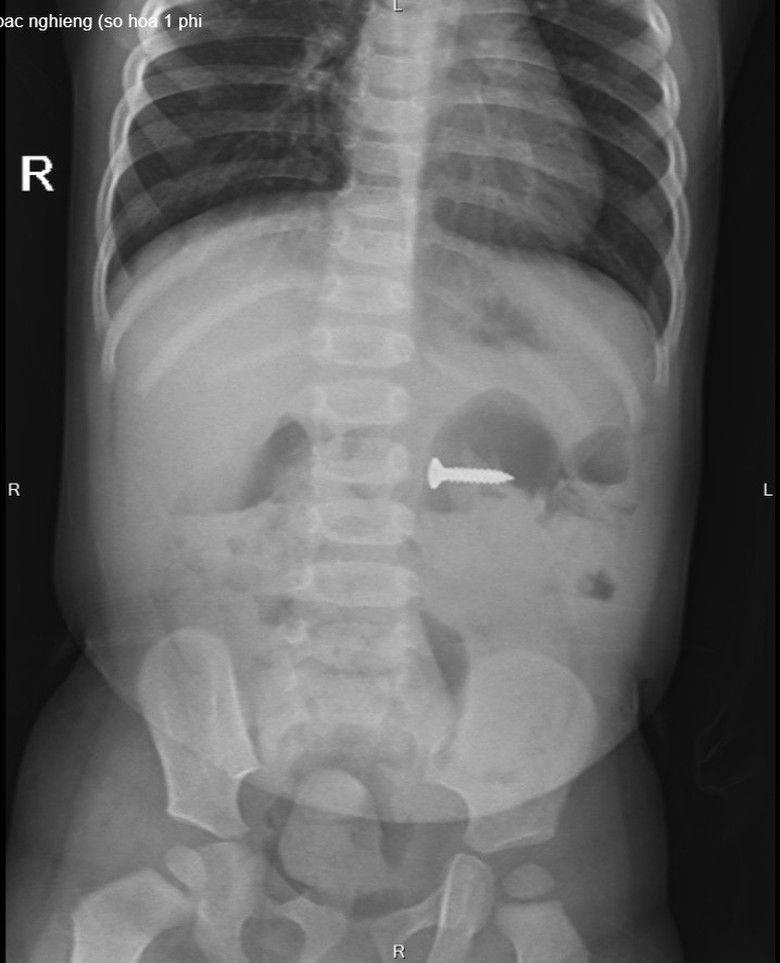

Hình ảnh chụp XQ phát hiện đinh vít nhọn nằm trong dạ dày của trẻ.

Tại Bệnh viện Sản nhi tỉnh Phú Thọ, các bác phát hiện dị vật đinh vít sắc nhọn kích thước 2 cm trong dạ dày. Với tính chất sắc nhọn, nếu không loại bỏ kịp thời, đinh vít có thể gây tổn thương đâm thủng thành ruột, dạ dày, thậm chí có thể gây tổn thương nhiều vị trí mà chiếc đinh đi qua.